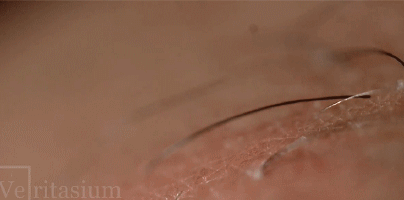

原理:上图记录下了激光脱毛的过程:通过短暂、快速的红外激光脉冲照射皮肤,使体毛中的黑色素更多吸收能量,从而损毁毛囊中生成毛发的毛母细胞,达到永久脱毛的目的,同时周围的浅色皮肤受影响较小。图中产生的“烟雾”实际上是细胞中的水分蒸发产生的水汽。

9 o" N, ~2 f+ ]5 U! q花絮:激光脱毛以黑色素作为“靶子”,它使用了黑色素会较多吸收能量,同时其他皮肤组织吸收能量较少的波段。因此,它在皮肤颜色浅、毛发颜色深的人身上效果最好。

; Y3 Y8 [/ H0 x: N' J9 C8 d录制者:Veritasium% k: B* p1 Q* A& O  S+ N; d